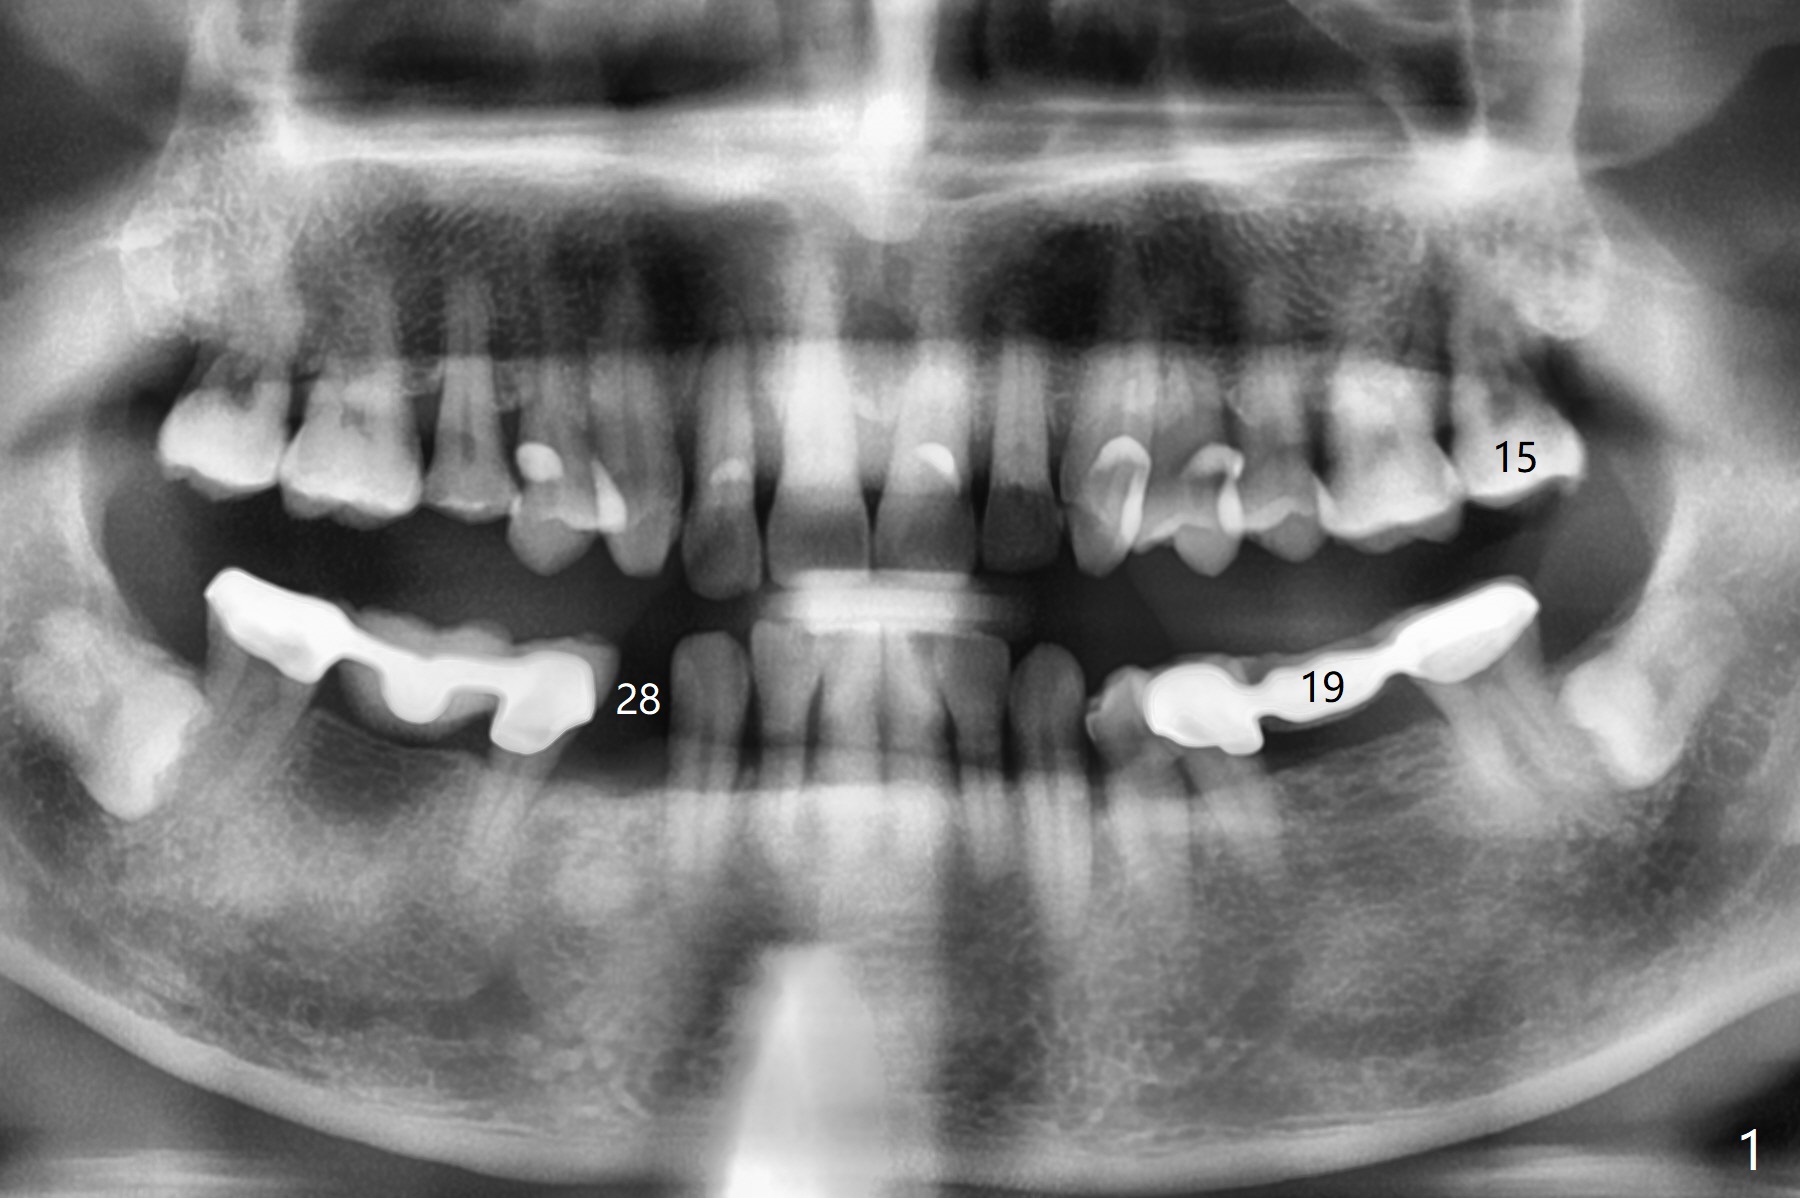

A 62-year-old man with sign of bruxism (#19 porcelain chip (Fig.2), 28 fracture/extraction) complains of severe mastication pain at #15 (Fig.1). More severe pain is elicited when the buccal cusps bite on a bite stick than the palatal one (Fig.3 with suspicious crazing lines). CT shows bone loss around the palatal root (Fig.4 P). A 5x11.5 mm implant will be placed immediately (Fig.5). The bone at #28 is able to hold a 3.5x13 mm implant (Fig.6). It is extremely difficult to take photos for 2nd molar crack line with a regular camera (Fig.3). The Shining Oral Scanner acts additionally as an intraoral camera. As a busy clinician, I do not have time to take photos for #19 porcelain chip. My assistants take over the task. After work, I am able to have bumper harvest. With the information just mentioned, I will be in a better position to present a more comprehensive treatment plan to the patient when treatment at #15 is finished: remove #18-20 bridge, place an implant at #19 and fabricate new crowns at #18 and 20.